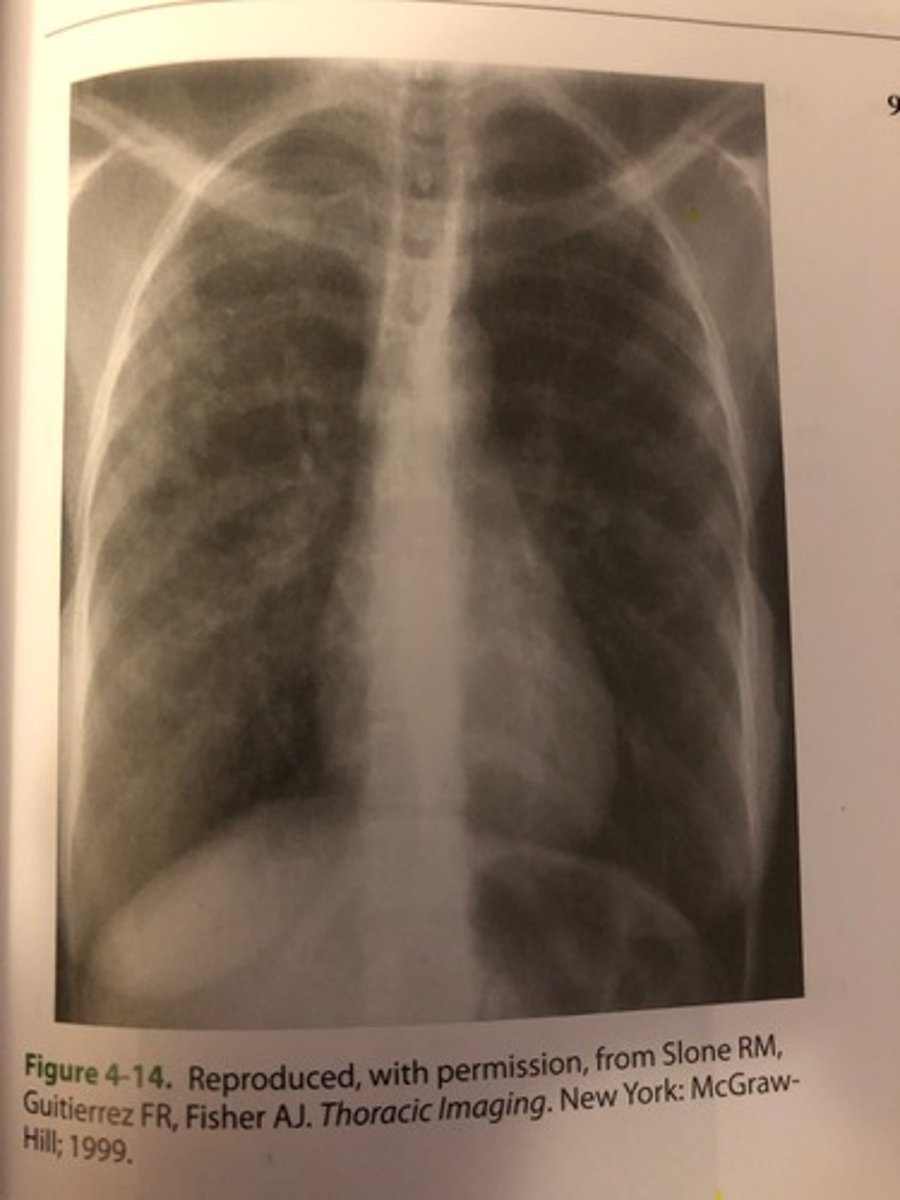

The PA chest image shown in Figure 4-14 exhibits which of the following qualities?

1. Adequate penetration of the heart

2. Long-scale contrast

3. Adequate inspiration

A. 1 only

B. 1 and 2 only

C. 2 and 3 only

D. 1, 2, and 3

(D) 1, 2, and 3